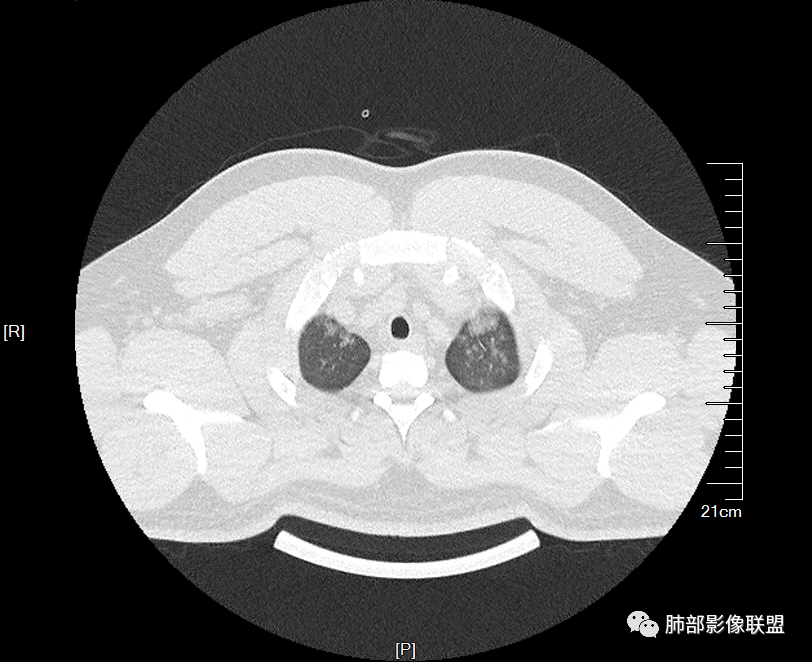

多发GGO结节,边界清,以全小叶、小叶中心为主:

GGO背景

小叶间隔增厚,无明显重力趋势

少量积液,脂肪肝

中轴间质稍增厚

细网格也明显

中轴间质增厚,小叶间隔增厚,小叶内间质增厚,部分重力作用,双侧对称,胸水,按理淋巴道回流受阻有